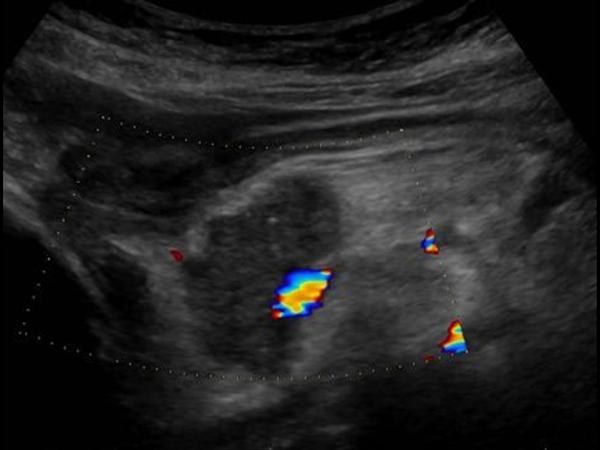

УЗИ диагностика кольцевидной поджелудочной железы: что важно знать